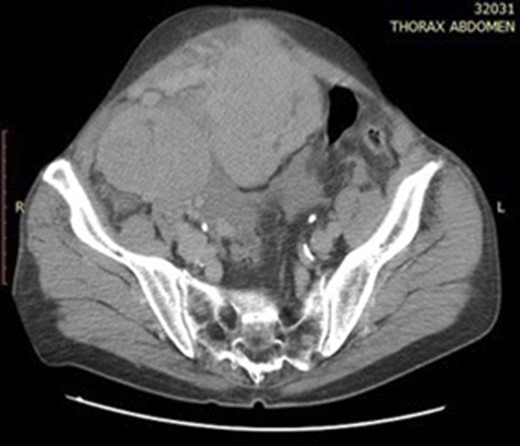

A 72-year-old gentleman presented to our unit with a recurrent mass of the anterior abdominal wall. This mass appeared gradually over several months causing a dull pain. No other symptoms were described. Clinical examination revealed a 11 × 10 cm soft and well defined, palpable mass on the right side of the abdominal wall (Fig. 1). Computer tomography (CT) of the abdomen presented several space-occupying lesions in the peritoneal cavity, the right side of the lower pelvis and the rectovesical pouch, measuring 11 × 10.4 × 10.7 cm, 8 × 6.5 cm and 7.5 × 5.7 cm, respectively (Figs 2 and 3). Due to compression, the veins of the anterior abdominal wall presented dilated. Thorax CT scan revealed no tumour.

Abdominal CT scan showing two hypervascular lesions in the abdomen.